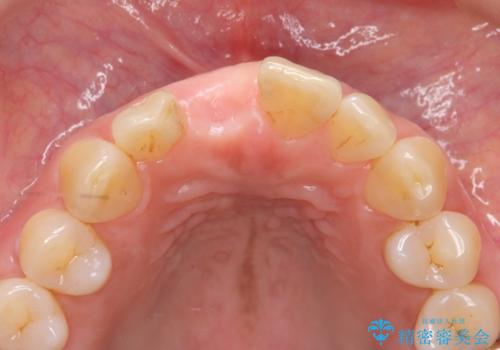

前歯のインプラントを審美的に仕上げるには、インプラント周囲に十分な骨の量と厚みのある歯肉、そして埋入位置の精密な位置付けが重要です。